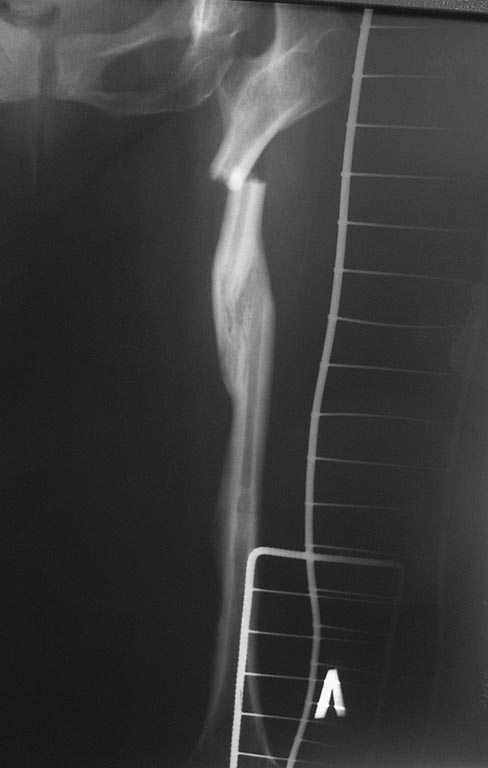

Больная Х, 38 лет. В 3-х летнем возрасте оперирована по поводу

врожденного вывиха левого бедра с иммобилизацией гипсовой повязкой.

Из-за контрактуры коленного сустава разработка на аппарате внешней

фиксации Волкова-Оганесяна. В 13-ти летнем возрасте остеосинтез

аппаратом Илизарова по поводу перелома бедра. До последней травмы

больная работает специалистом отдела кадров. ходила с ортопедической

обувью, без вспомогательных средств (трость). Травма ДТП. после травмы

мы проводили скелетное вытяжение. После предоперационной подготовки

выполнена операция: Закрытая репозиция блокированный синтез левого

бедра. компресивным плечевым стержнем №6. т.к подготовленный

универсальный стержень для бедра диаметром 8мм не поместился. римерами

удалось расширить до 7-го размера.